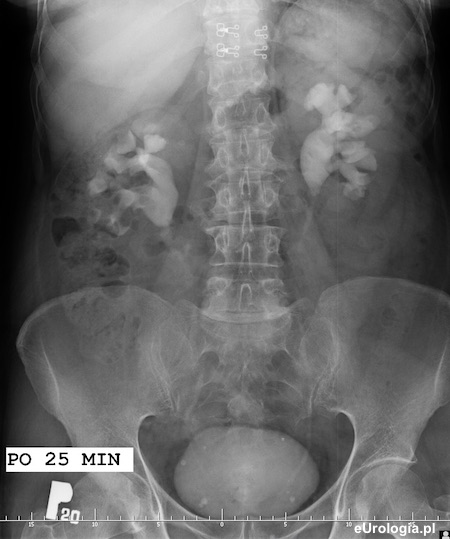

Zakontrastowane układy zbiorcze obu nerek po 25 minutach od podania środka kontrastowego. Widoczny zarys pęcherza moczowego i dolny odcinek lewego moczowodu.